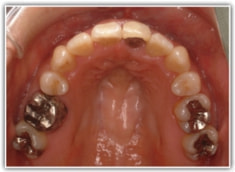

治療開始時

治療開始から約1年後

修復歯、補綴歯もあります。下顎8番が水平埋伏しています。

下顎8番は、両側抜歯済みです。